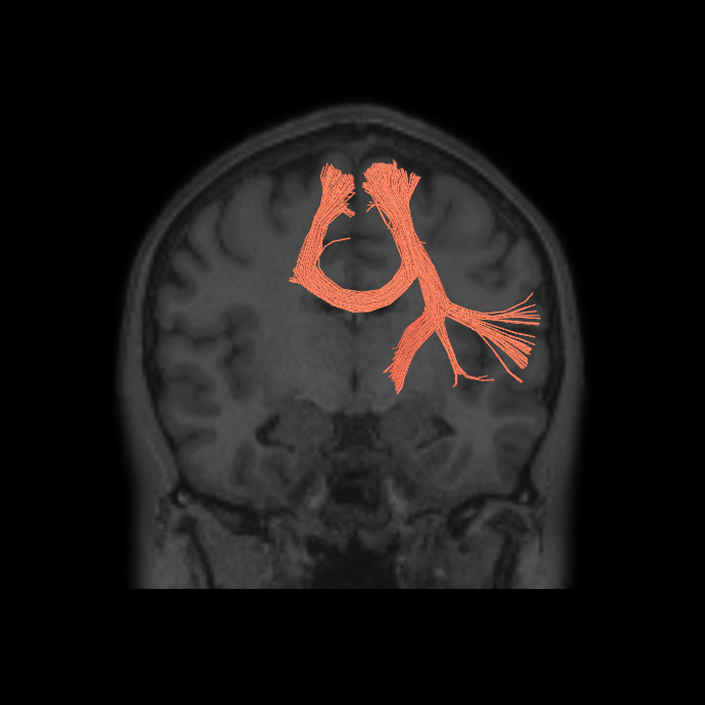

Connectome Guide

Language Network

Why we think this network is worth considering in decision making:

Disturbances of language have been linked to anatomic disruption of the human language network architecture for nearly 150 years.

Evidence that this network is responsible for useful function in humans:

While details regarding its exact organization are still in refinement, the basic details regarding the anatomy of the human language system have been non-controversial for many decades, and there is a long and robust history of using models of the language system in clinical decision-making spanning back a very long time.

Exploring the language organization in the brain began in the mid-19th century with Broca’s and Wernicke’s studies on patients with defined brain injuries and lesions in the mid-19th century.1,2 Further studies identified a neural tract, the arcuate fasciculus, for connecting Broca’s and Wernicke’s areas being one of the major components of language processing in humans.3 Later on, more studies confirmed and expanded these findings using additional techniques such as cortical intraoperative mapping,4 and subcortical mapping,5 and neuroimaging using DTI and fMRI. Using DTI, Rilling et al., (2008) found a noticeable temporal projection of arcuate fasciculus that is much smaller or absent in non-human primates.6 Further studies reported a strong left lateralization of arcuate fasciculus in humans.7

Additional invasive tests have been described to study impact on networks for clinical decision making. Historically injecting sodium amytal into one carotid artery (Wada Test) has been the gold standard for finding out the language lateralization in the brain.8 Studies found a very strong correlation between Wada test and language lateralization.9 More recently, similar findings have emerged using non-invasive neuro-imaging techniques. One study reported fMRI superiority over Wada test predicting postoperative language function in patients when fMRI and Wada test are not consistent with each other.10 Moreover, a recent guideline by the American Academy of Neurology suggested fMRI may be considered as a replacement of Wada test in epilepsy.11

Consequences of damage to this network:

Evidence that damaging this network causes neurological decline.

Several studies demonstrated aphasic impairment as a result of damage to this network in stroke patients, epilepsy patients, and tumor patients.12,13,14

Lately, speech network has been successfully mapped using rs-fMRI in an aphasic patient with left temporal tumor even in the absence of cognitive function. In the study, patient was scanned before and after a seizure that causes aphasia for several days.15 In aged patients it was found that higher functional connectivity in the left language areas associated with higher scores in behavioral tests, this finding suggests a role for functional preservation in these areas.16